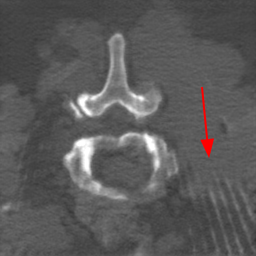

Cone-beam computed tomography (CBCT) has been widely used in spinal surgery as an intraoperative imaging modality to guide the intervention [19, 20]. However, compared with conventional CT, intraoperative CBCT images have pronounced noise and poor tissue contrast [13, 15]. Moreover, it is common to have metallic objects (such as pedicle screws) present during operation, which cause metal artifacts and degrade the quality of CBCT images [12]. To facilitate spinal surgery planning and guidance, it is of great importance to accurately identify the vertebrae [1]; yet the poor CBCT image quality makes it challenging to delineate the vertebra shape even manually.

This paper aims to design a computational method to automatically segment vertebrae from clinical CBCT images, not from cadaver images as in [12]. Since it is challenging to create a large number of CBCT images with annotations and yet high quality (artifact-free and high contrast) spinal CT datasets with vertebra delineations are easy to access [17], we investigate the feasibility of learning a CBCT vertebra segmentation model using unpaired CT images with annotations as in Fig. 1. Such learning has to overcome two obvious gaps: (i) the modality gap between CT and CBCT, that is, the image appearances look different even for the same content; and (ii) the artifact gap as the CT image is artifact-free and the CBCT is artifact-laden. In other words, we have to address three heterogeneous tasks of vertebra segmentation, artifact reduction, and modality translation all together in order to derive a good solution.